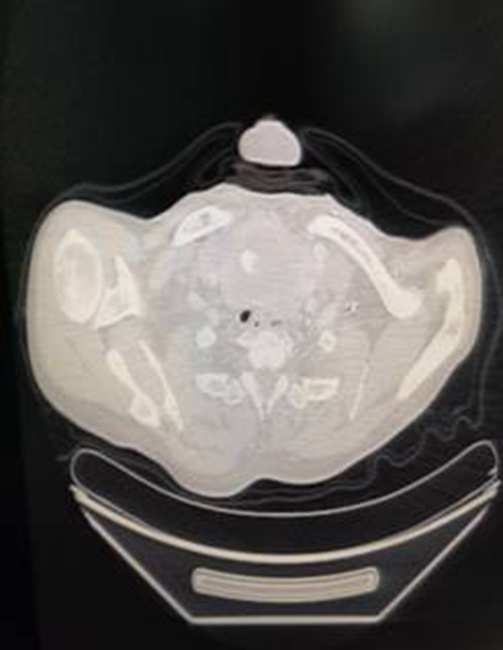

对于这种气道狭窄的全麻病人,气管导管是他的生命线,麻醉后插管和拔管的风险都很大。从颈胸部CT上评估,老杨气管最狭窄处直径在6-7mm,也可能更细,只能选择小儿的气管导管。对于老杨来说如果这根管子过不了气管最狭窄处,就预示着希望被扑灭,只能“坐以待毙”。就算插管顺利但是术中探查发现肿瘤切不掉或者气管严重软化塌陷,这种情况下维系生命的气管导管很可能拔不掉,老杨也会因此命悬一线。在党晓东主任和陈军副主任的带领下,手麻二部的全体医务人员高度重视,党晓东主任多次会诊观察病情变化,并在手术前一天和当日清晨,组织了两次全科大讨论,制定了安全缜密的麻醉方案,并对可能出现的意外情况,进行预案桌演,力求做到万无一失。